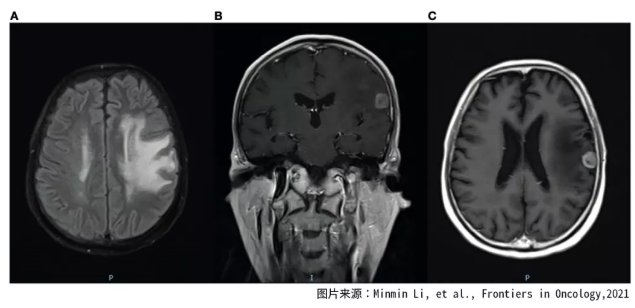

对脑转移的患者,放疗是最常用的治疗措施。对于多发性脑转移的患者,往往使用全脑放射治疗。但是由于放射的危害性,以及潜在的认知下降风险,全脑放射治疗往往只有一次机会,而且五年之内往往不能再次进行全脑放疗。因此,是否使用全脑放疗,什么时候使用全脑放疗,是一个困扰人的难题。 下面的这个案例报道中,患者接受了重复性的全脑放射治疗,获得了长达12年的生存期。最为重要的是,整个生存期内,患者的生活质量很好。 2006年5月,一名42岁的中国男性患者因为咳嗽、咳痰而就诊,纤维支气管镜检查显示左肺下叶部位有腺癌细胞。 磁共振MRI检查表明肿瘤已经转移到脑部。由于脑部有多个转移灶,不能使用伽马刀治疗。患者属于四期肺癌,也失去了手术治疗的机会,医生建议患者使用化疗联合放疗作为治疗措施。 图1. 2011年7月-9月放疗前后脑核磁检查结果 在进行了一个周期的吉西他滨联合顺铂的化疗后,对患者的原发病灶进行了放射治疗,使用的是二维放射治疗技术,总剂量为70格瑞,治疗分为35次。对脑部进行了全脑放射治疗,共20次分割,总放射剂量为40格瑞。 放疗之后,患者接受了三个周期的化疗,化疗用药为紫杉醇和顺铂。经过这些治疗,患者的症状明显减轻,血液的肿瘤标志物明显下降。放疗后的肿瘤病灶被评估为完全缓解(可见肿瘤病灶消失)。这种情况持续了近五年时间。 2011年7月,患者因为脑部转移瘤复发而入院,患者表现为意识障碍。PET-CT扫描显示脑外的肿瘤病灶稳定。 图2. 2016年1月脑放疗之前的核磁结果 患者每天使用150毫克的厄洛替尼进行治疗,同时使用三维放射治疗,再次进行了全脑放射治疗。总剂量为30个格瑞,分15次完成。放疗完成之后,患者进行了四个周期的尼莫司汀和厄洛替尼的维持治疗。2011年9月,脑部核磁发现转移灶显著缩小,患者的病情得到了有效控制。 2016年1月,时隔近五年,患者出现了病情进展的迹象。医生使用18毫米准直器对患者的脑单病灶进行了放疗,放疗靶区中心剂量为25.4格瑞,治疗评估为部分缓解。但是3个月之后,出现了新的脑部病灶。由于放疗后短时间内复发,因此选择了尼莫司汀化疗,治疗时间为四周,作为姑息治疗方式。由于后期反复的肺部感染严重影响了患者的健康, 患者于2018年8月不幸因呼吸衰竭而去世。 图3.2016年4月放疗之后再次出现脑进展 尽管在治疗期间进行了多次放射治疗,但是患者的生活质量良好,即使进行了二次全脑放射治疗,也没有出现严重的神经认知缺陷和其他严重的不良反应。 启示 回顾这名患者的治疗过程,曲折而又艰难。不断反复出现的脑转移灶,让患者不得不经受两次全脑放疗。万幸患者在治疗后,得到了有质量的生存期。 医生在制定治疗方案时,需要根据患者的整体情况,考虑放疗的剂量,部位等等,这需要医生具备专业的知识技能和丰富的临床经验。否则,同样的放疗,同样的设备,治疗效果也有可能会出现差异。 本案例中患者的驱动基因状态我们无法得知,如果有可能,也许可以通过入脑效果好的靶向药物治疗,这样对患者的脑部病灶进行一些控制,从而减少脑放疗的次数和剂量,患者可能会因此受益更多。 参考文献: Minmin Li, et al., Reirradiation of Whole Brain for Recurrent Brain Metastases:A Case Report of Lung Cancer With 12-Year Survival, Frontiers in Oncology,2021晚期脑转移肺癌患者的抗癌历程